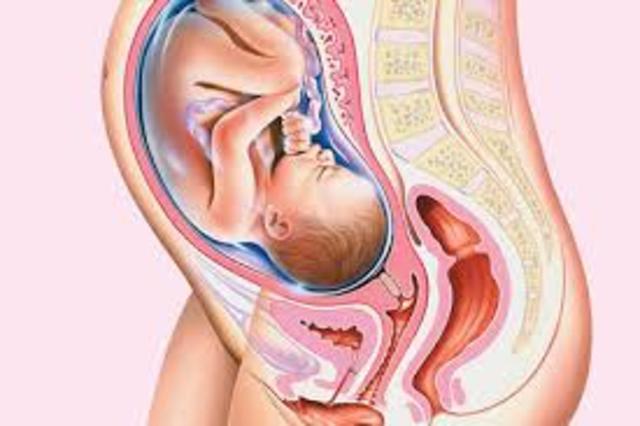

• 7th Month (Weeks 30-31)

7th Month (Weeks 30-31)

Week 30

Size of a cabbage

Growth in length will slow down but baby will continue to gain weight until born

Baby will respond to light by turning his or her head when a flashlight is place at the bump

Eyesight is still developing

Amniotic fluid surrounding the baby is increasing

Week 31

Size of a coconut

Starting to look more like a newborn

Wrinkled skin becomes more smooth

As baby grows room in the womb becomes limited this is where baby will assume the classic fetal position